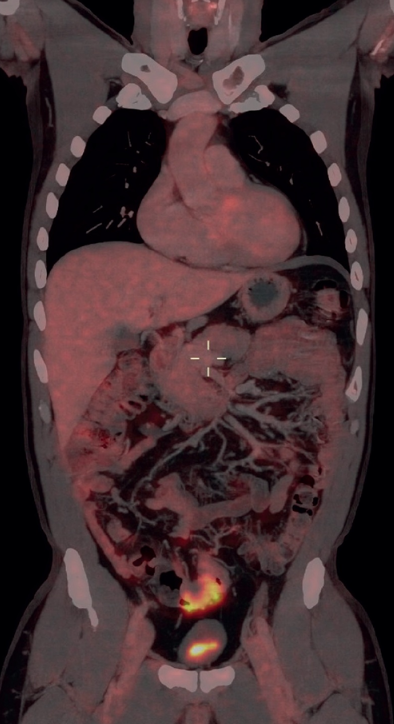

PET/CT(图1)显示乙状结肠壁增厚,患者被转诊进行结肠镜检查,随后接受了机器人辅助腹腔镜乙状结肠切除术。

图1. PET/CT检查